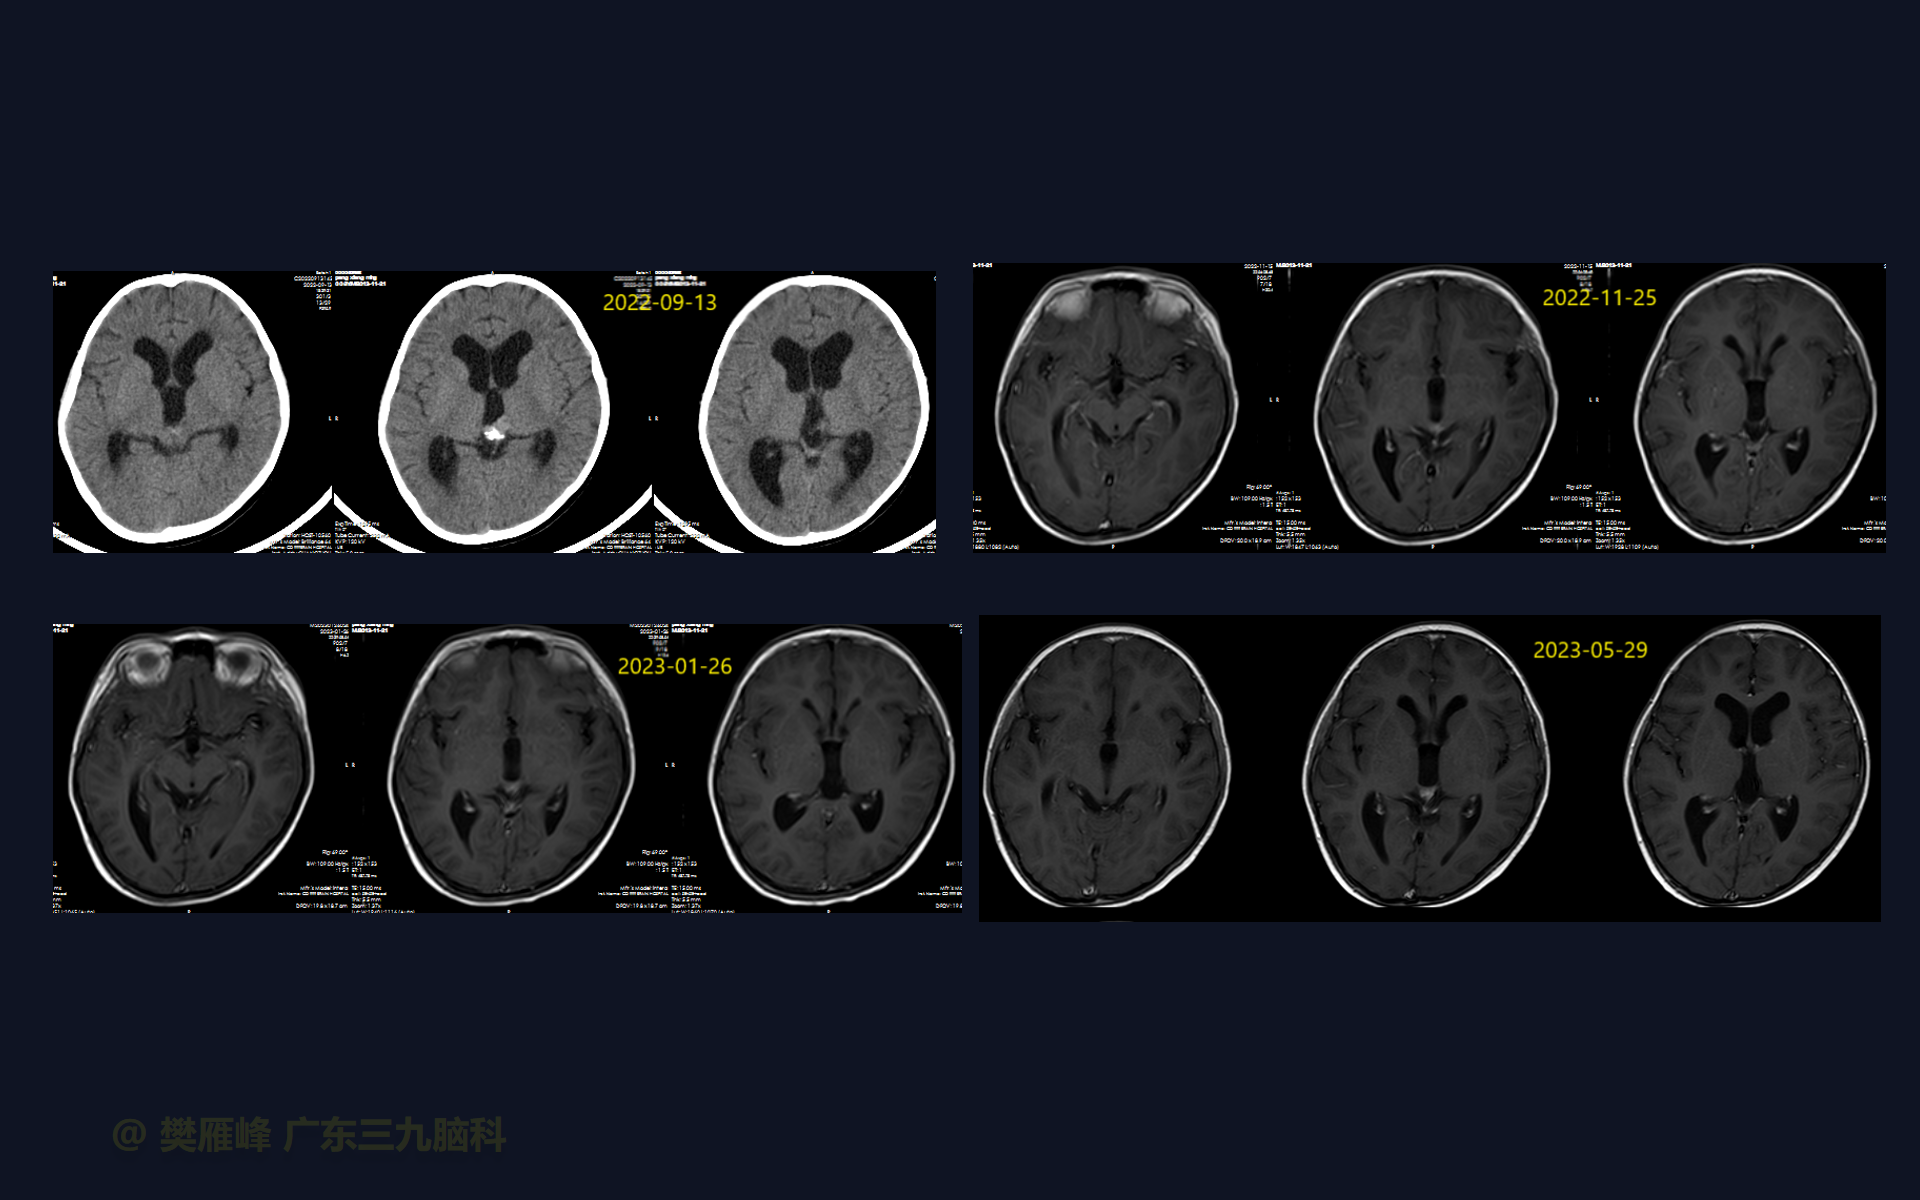

在这个二维手术视频中,展示了2例神经内镜下三脑室底造瘘+活检治疗三脑室后部肿瘤的方法。患者均为三脑室后部病变导致的梗阻性脑积水,病理结果1例为生殖细胞瘤,1例为淋巴瘤,在经过术后的放化疗病情均得到控制,生活质量满意。我们展示了安全的病变活检和第三脑室造瘘的技术要点,以最大限度减少术后继发脑积水和早期并发症。